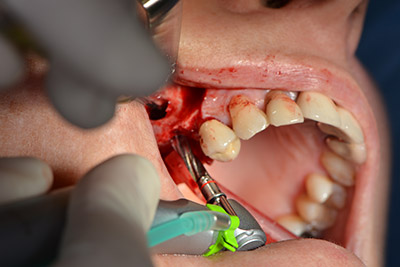

The classic incision (crestal, buccal relief) and the preparation of the mucoperiosteal flap enabled a good overview.

Sky implants (bredent) were used this case. The surgical protocol of these, specify pilot drilling at about 1200 rpm (Fig. 9).